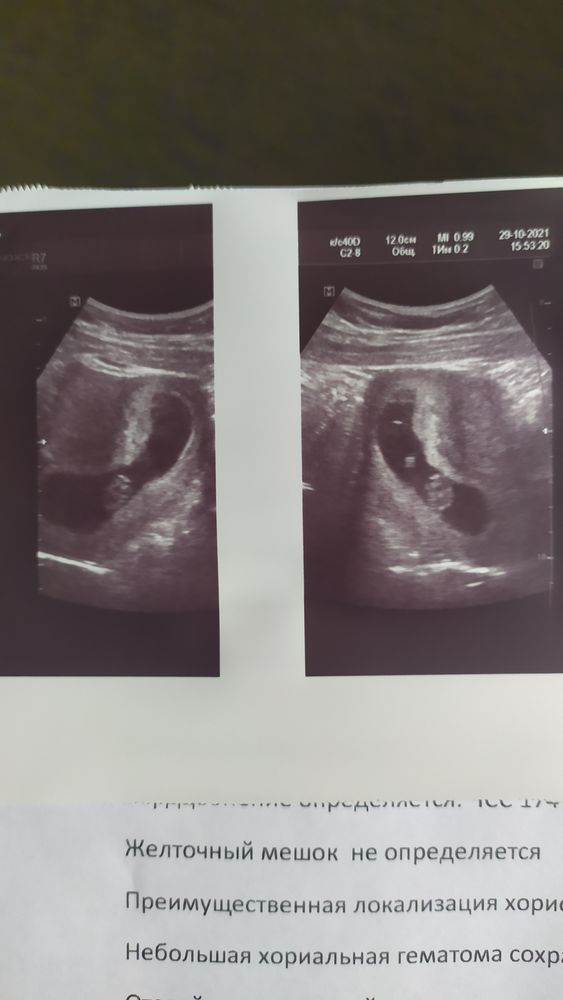

Узи на 9 неделе, нет желточного мешочка

Думаю что-то узистка напутала, и мне кажется я на втором фото вижу жм. Мне кажется если бы не было жм, то б до 9 недель не прогрессировала бы. Чсс у вас хорошее, переделайте его лучше

Irina Ro, да, правдо вагинально смотрели 4,5 мм было за 10 дней до этого узи

Анастасия Мамедова, в таком случае не переживайте, никуда ваш жм не делся, просто его не увидели

Мне кажется, что она просто что-то перепутала. ЖМ, конечно, к 1 скринингу рассасывается, но странно конечно.

Mi Mi, смотрела через живот, может не увидела из за тонуса?

Я думаю все у вас прекрасно и КТР и ЧСС. Переделайте узи в другом месте для своего спокойствия и сделайте акцент на желточном мешочке. Пусть посмотрят

Кристи, я после него сразу в жк пошла к гинекологу, отправила домой, до этого за день назначила утражестан и покой. Я лежала на сохранении уже 2 раза и это уже 9 УЗИ😭